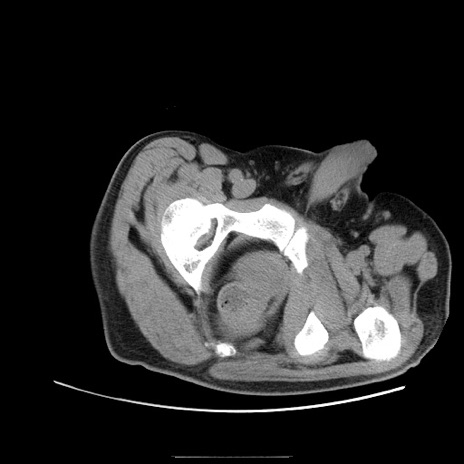

症例22(横断像)

【症例】50歳代男性

【主訴】腹痛

【現病歴】AVMからの被殻出血のため回復期リハ病棟入院中。 本日午後3時頃急に下腹部痛が出現した。

【既往歴】AVM、被殻出血、虫垂炎、高血圧

【身体所見】意識晴明、左半身不全麻痺、会話の理解は良好、36.5°C、腹部:膨隆、全体に板状硬、下腹部正中に圧痛点あり、反跳痛-、筋性防御不明、右下腹部にope scar

【データ】WBC 9400、CRP 0.06